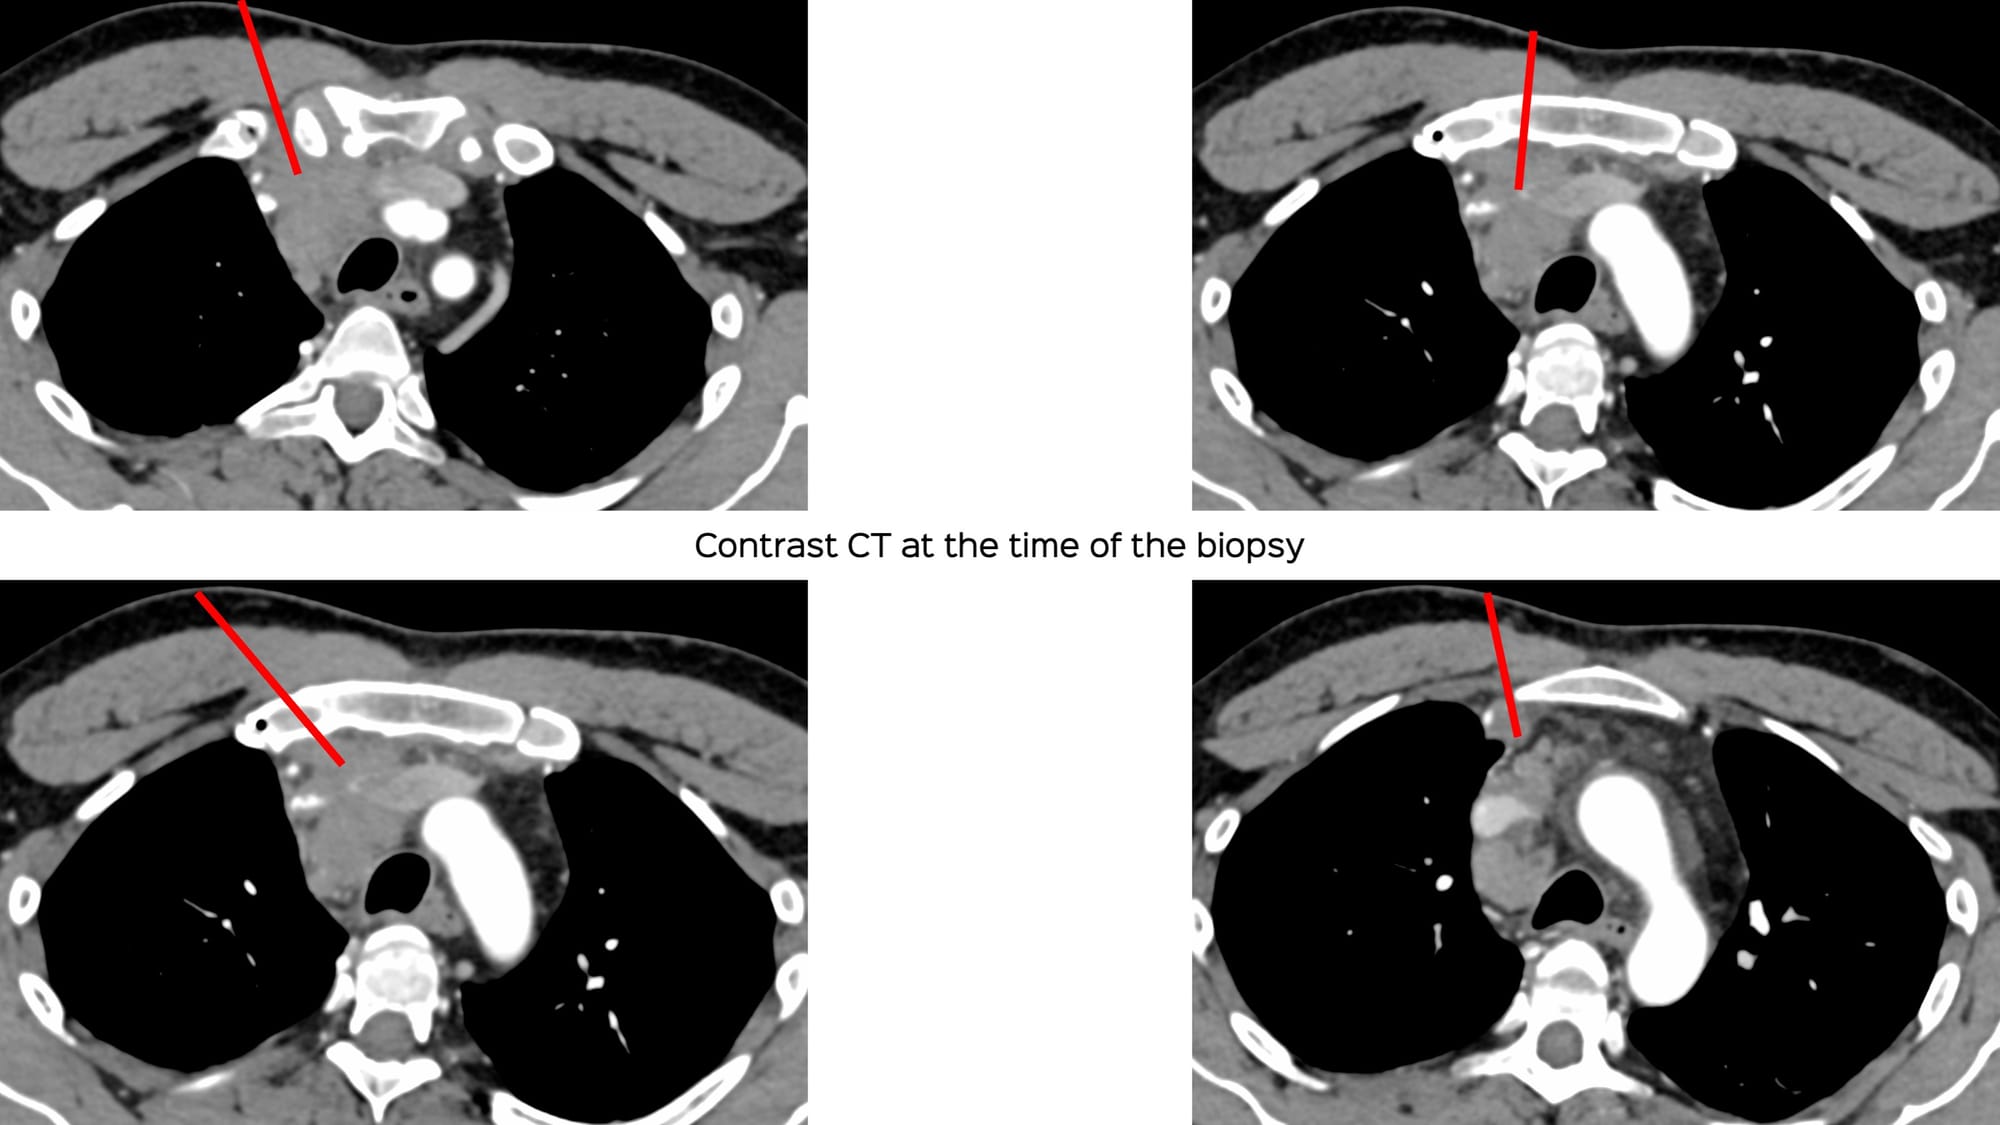

After I had decided on the route, I found that the situation had changed during the CT scan obtained just at the time of the biopsy.

Which route will you take for the biopsy?